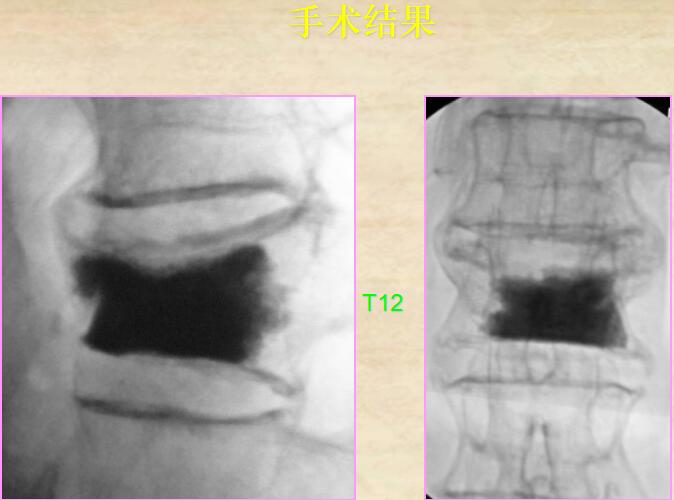

5、手術(shù)結(jié)果